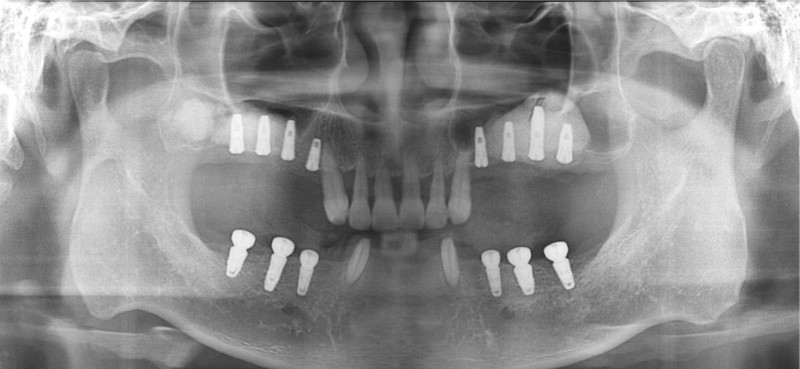

상악동거상술 Sinus

중간과정 ▼